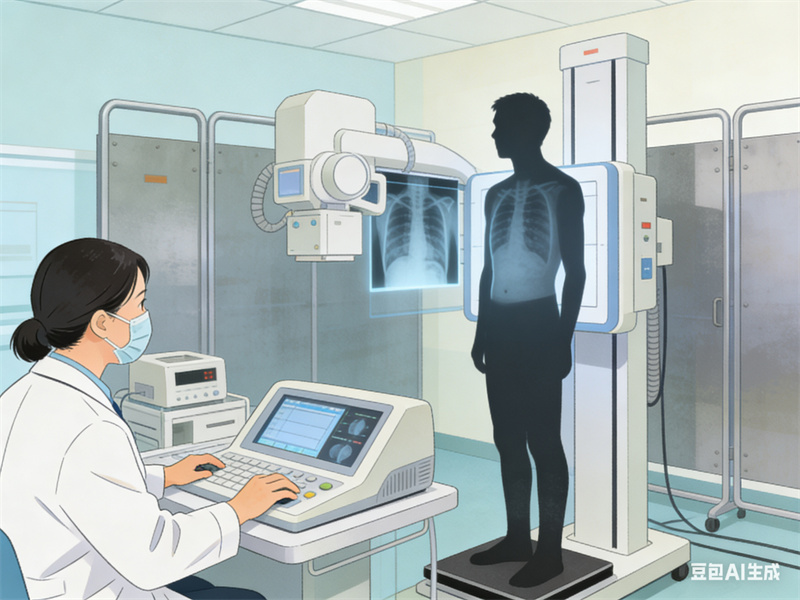

1.肺功能检查:是判断气流受限的主要客观指标,对慢性阻塞性肺疾病诊断、严重程度评价、疾病进展、预后及治疗等有重要意义。

2.影像学检查:胸部X光或CT检查可评估肺部的结构变化。

3.血气检查:掌握氧气和二氧化碳的浓度,对判断呼吸衰竭的类型有重要价值。